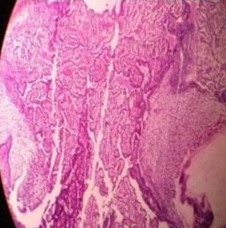

Figure 1: (40× magnification): Invasive carcinoma in the dermis and subcutaneous tissue with desmoplastic stroma and pseudoepitheliomatous hyperplasia.